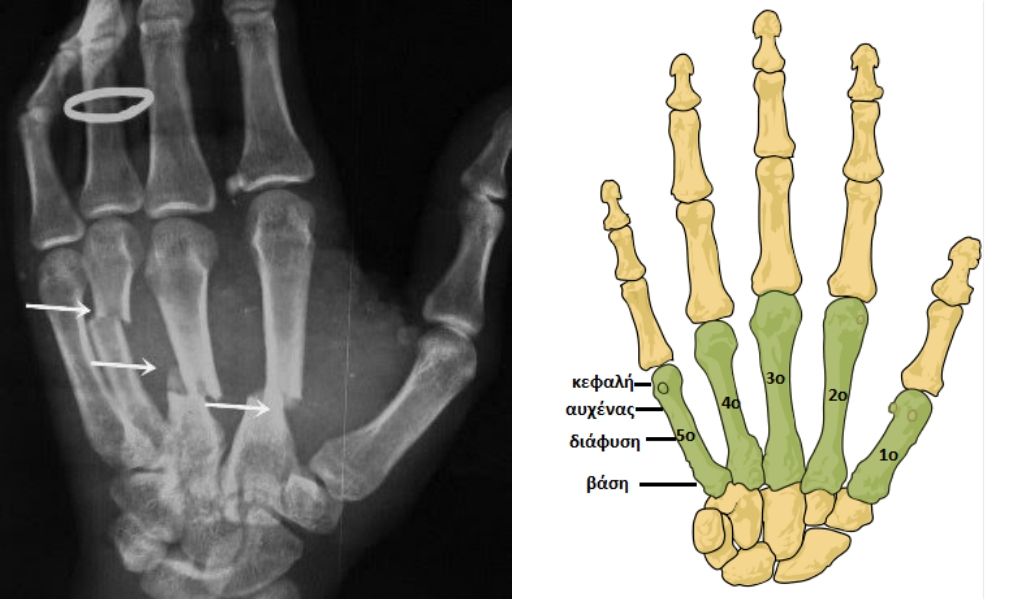

«Ο Τι Τζέι Μπρέι υπέστη κάταγμα στο τέταρτο μετακάρπιο του δεξιού του χεριού κατά τη διάρκεια της σημερινής (17/3) προπόνησης και αύριο (18/3) θα υποβληθεί σε χειρουργική επέμβαση στο νοσοκομείο “ΥΓΕΙΑ”».

Για να δείτε που ακριβώς τραυματίστηκε ο Αμερικανός προσέξτε την παρακάτω φωτογραφία

Τα πιο κοινά συμπτώματα είναι πόνος (αυτόματος ή με την πίεση), το οίδημα στη ραχιαία επιφάνεια, η παραμόρφωση, και η αδυναμία της παλάμης να κλείσει ή να κρατήσει αντικείμενα. Καθώς δεν μπορεί να κινηθεί το δάκτυλο (ή τα δάκτυλα). Επειδή τα μετακάρπια βρίσκονται υποδόρια πολλές φορές συνυπάρχει και τραυματισμός του δέρματος.

Τα κατάγματα που είναι στη βάση των μετακαρπίων, δηλαδή εκεί που γίνεται άρθρωση με το αντίστοιχο οστούν του άπω στοίχου του καρπού, εκτός του αντίχειρα, εάν δεν υπάρχει στροφική παραμόρφωση μπορούν να αντιμετωπιστούν συντηρητικά. Αυτό σημαίνει ακινητοποίηση σε νάρθηκα για 3-4 εβδομάδες και σταδιακή κινητοποίηση ώστε να προληφθούν οι δυσκαμψίες. Σταθερά στη μεγάλη τους πλειοψηφία είναι και τα κατάγματα στη διάφυση των μετακαρπίων – πρόκειται για το σημείο που χρησιμεύει για την πρόσφυση μυών, τενόντων και συνδέσμων. Και σε αυτή την περίπτωση η συντηρητική αντιμετώπιση με εφαρμογή γύψινου ραχιαίου νάρθηκα έχει πολύ καλά αποτελέσματα. (Πηγή: minisco.gr)